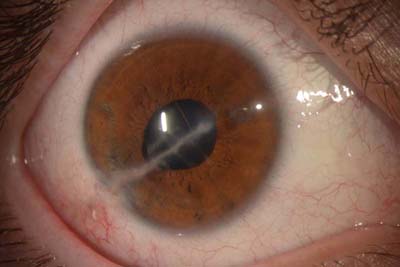

Ojo Sano

Ojo Sano, Foto tomada en Lampara de Hendidura